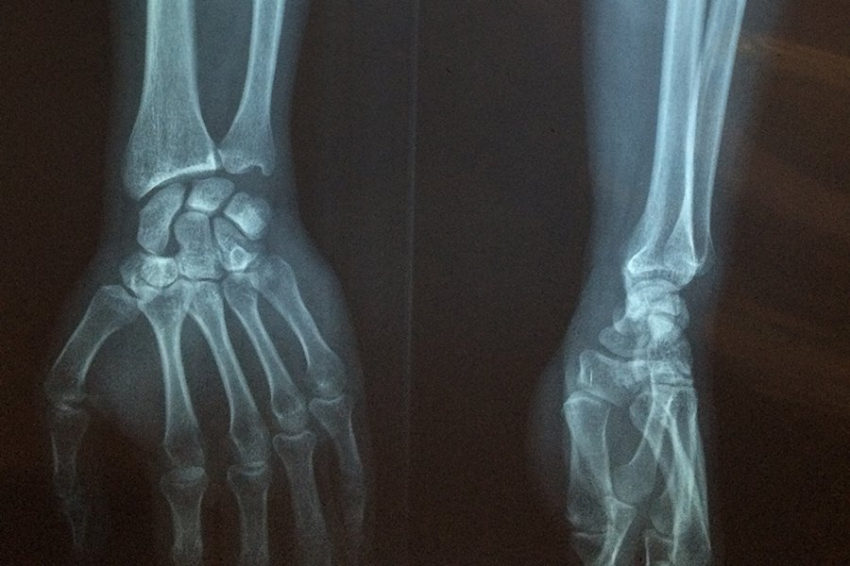

Международная группа исследователей разработала новый метод, способный запустить природные процессы регенерации костной ткани. Центральным элементом этой технологии стал особый рецептор GPR133. Учёные уверены, что полученные данные могут кардинально изменить подход к терапии остеопороза — заболевания, которое по-прежнему остаётся одной из наиболее значимых угроз для системы здравоохранения. Об этом сообщает 1RR.

Международная команда исследователей представила результаты работы, которые могут перевернуть представления медицины о восстановлении костной ткани. Учёные под руководством профессора Инес Либшер из Лейпцигского университета обнаружили, что рецептор GPR133 выполняет роль своеобразного стартового сигнала для остеобластов — клеток, отвечающих за формирование костей. Об этом сообщает издание Naked Science.

Открытие роли GPR133 уже называют одним из самых перспективных направлений современной биомедицины. Если результаты подтвердятся на людях, методы терапии остеопороза могут измениться радикально.